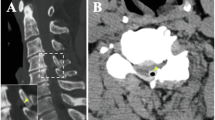

we report a Caucasian 37-year-old man who suffered a high-energy thoracolumbar spine trauma in a motorcycle accident with acute paraplegia. He presented ossification of the ligamentum flavum between the thoracic vertebrae T10 and T11 with a decrease in the diameter of the vertebral canal as the only pathological finding. We treated the patient with early surgical release before 72 h of trauma. We performed a posterior approach with hemilaminectomy and T10–T11 flavectomy. Arthrodesis was done with T10–T11 pedicle screws. Postoperative neurological status improved from ASIA Impairment Scale (AIS) A to C with severe functional dependence.